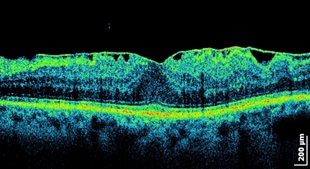

Огромный спектр заболеваний требует проведения подобных операций – сразу с картинками томографии:

Центральные «дырки» или макулярные отверстия;

Сморщивание сетчатки из-за появления над ней плотного слоя стекловидного тела, сращенного с ней (появление эпиретинальной мембраны, эпиретинальный фиброз);

Отслойка сетчатки;

А также диабет глаза – когда в стекловидное тело прорастают ткани с сосудами, кровящие и сморщивающие структуры внутри, кровоизлияния в стекловидное тело (например, из-за травмы или гипертонии), внутриглазные инфекции, ретинопатия у недоношенных и довольно много других неприятных состояний.